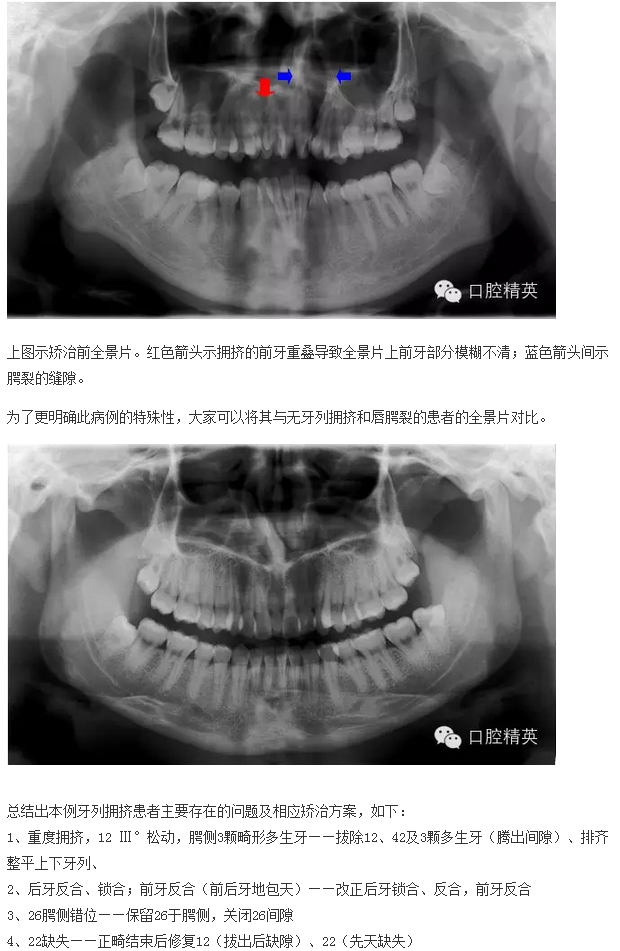

下面來(lái)個(gè)圖,震撼一下大家的心靈。